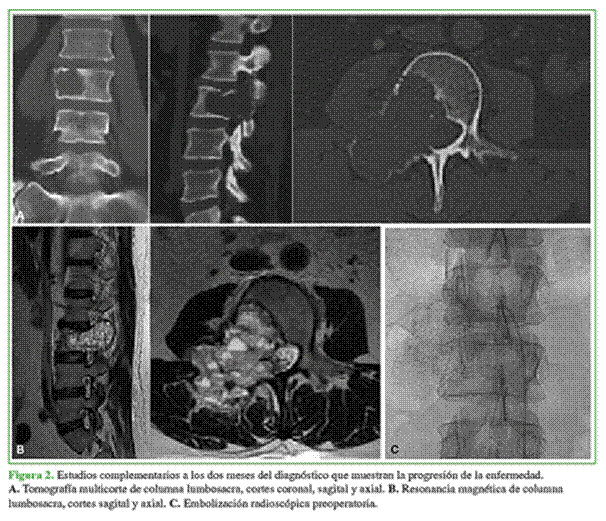

Se solicitaron otros estudios por imágenes, tomografía helicoidal y resonancia magnética, y se confirmó la ubicación de la lesión dentro de la vértebra. La biopsia por punción guiada por tomografía (Figura 1) confirmó el diagnóstico de QOA. A los dos meses de la consulta y los estudios, el quiste tuvo una evolución tórpida y los síntomas se incrementaron; por lo tanto, se solicitaron nuevos estudios en los que se observó la progresión e inclusive una fractura patológica en el cuerpo de L3 (Figura 2).

Se decidió evaluar las posibilidades de tratamiento para esta paciente y los puntos considerados fueron: que era una lesión benigna rápidamente progresiva, tipo G0III (agresivo) extracapsular y extracompartimental M0, según la clasificación de Enneking; la paciente no tenía síntomas de inestabilidad potencial en el momento del examen y sí presentaba trastornos neurológicos progresivos. Después de analizar la bibliografía, se optó por la embolización previa selectiva, 24 h antes de la intervención, un abordaje por vía posterior, la exéresis de la lesión intracompartimental con fenol como sustancia coadyuvante y fresado de la lesión, la liberación del saco dural y de las raíces de L2 y también de L3 con artrodesis de las vértebras L2, L3 y L4 (Figura 3).

A los seis meses del procedimiento, la paciente no tiene síntomas. La tomografía computarizada y la resonancia magnética de control (Figura 4) muestran una imagen compatible con recidiva local del QOA. Después de consultar la bibliografía citada en este artículo, se discutió el nuevo tratamiento con las siguientes opciones: nueva vertebrectomía de L3, inyecciones intratumorales de corticoides y calcitonina, embolización del tumor, administración de denosumab. Se optó por el tratamiento con denosumab 120 mg, dosis inicial, cada tres meses, por dos años. A medio término se realizó un control tomográfico y se constató la remisión y la calcificación de la lesión (Figura 5).